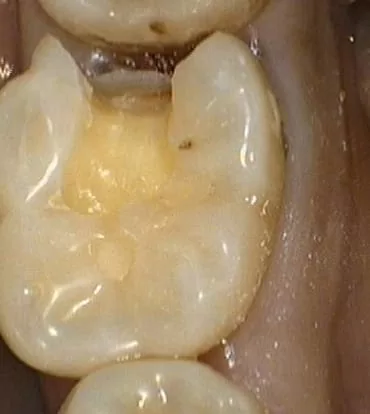

(圖一 治療前)

牙齒的鄰接面蛀牙,牙面已缺損